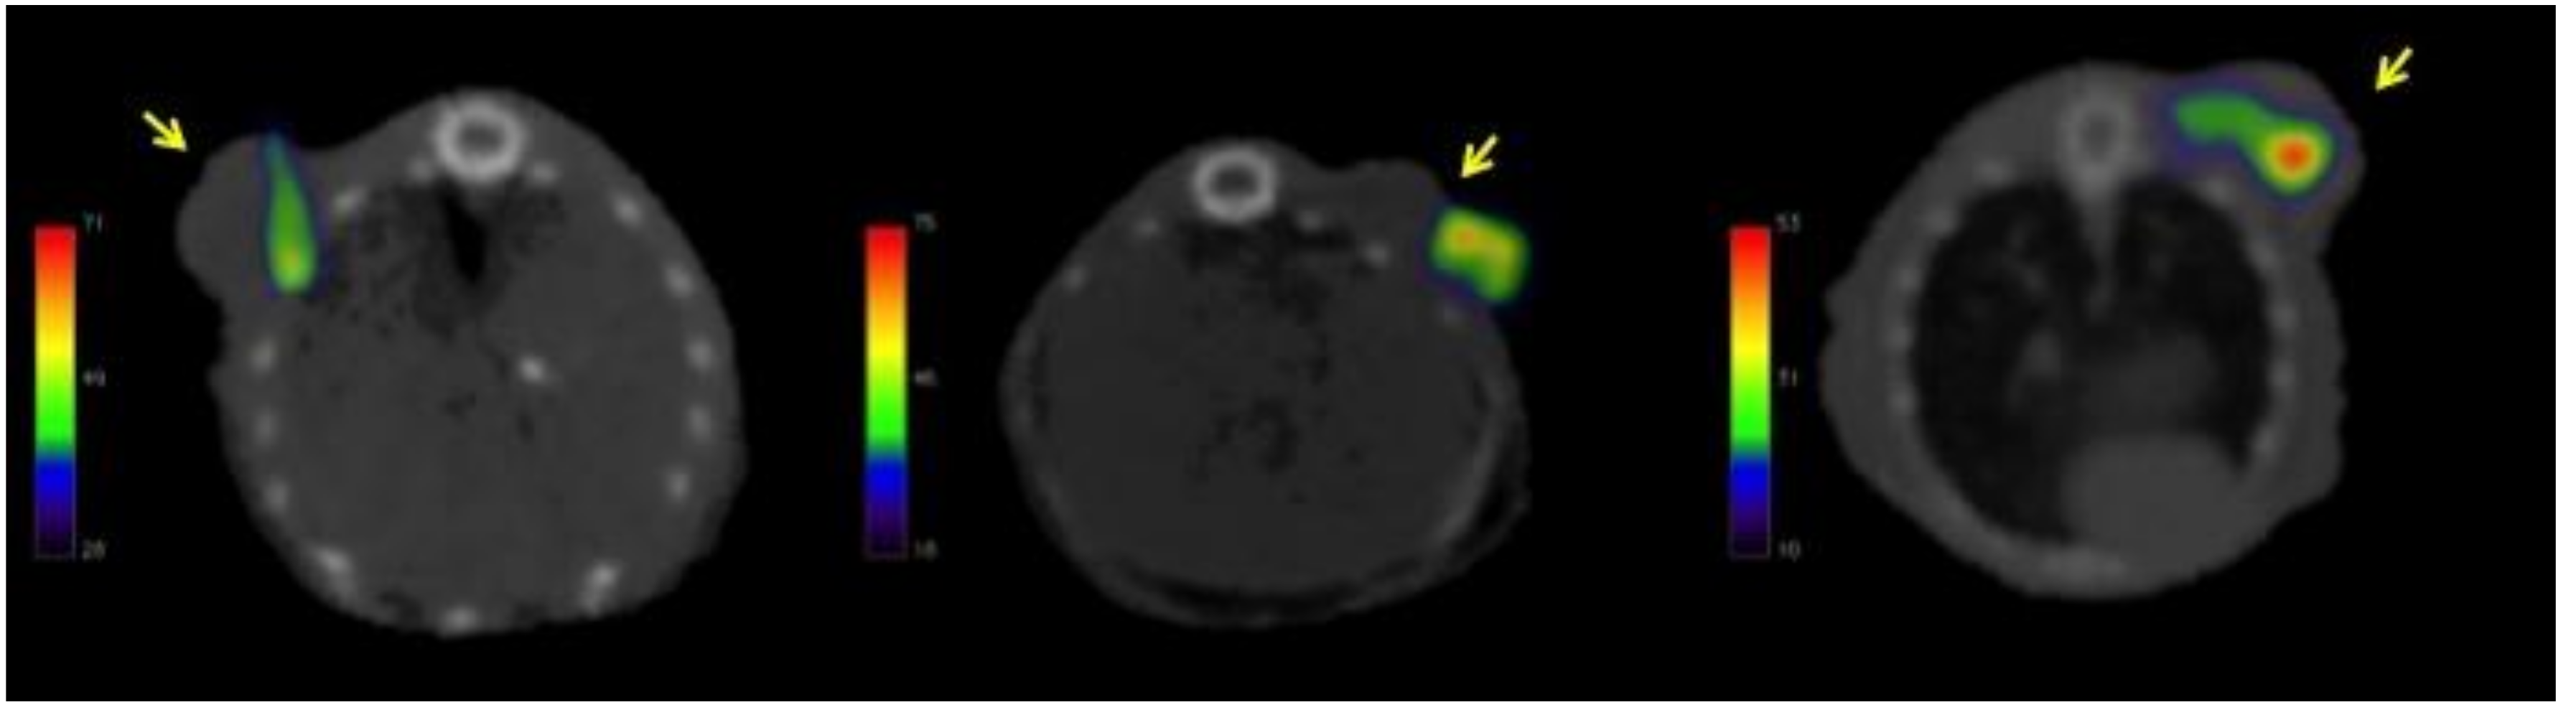

2.4. Biodistribution and Tumor Uptake in Mesothelioma Xenografts

4.8. Biodistribution and Molecular Imaging Studies